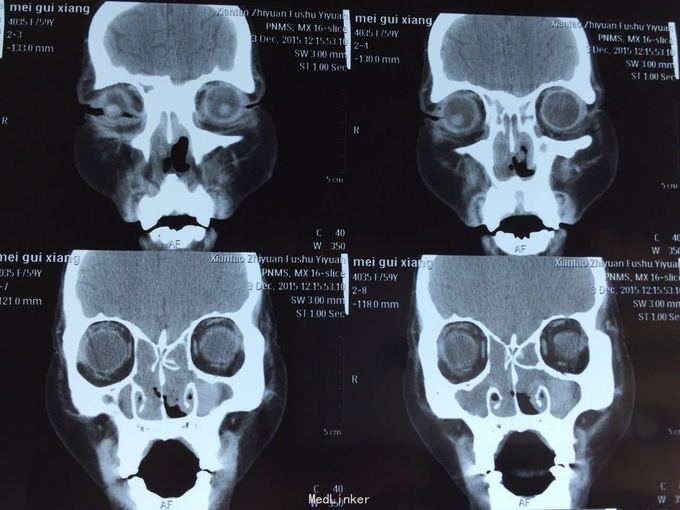

患者鼻塞分泌物增多,一年余,自诉曾于03年及09年两次鼻息肉摘除手术,现查鼻内镜双侧鼻腔可见大量息肉样物,鼻窦ct示全组鼻窦炎,鼻腔息肉。患者拟住院行第三次鼻息肉手术。